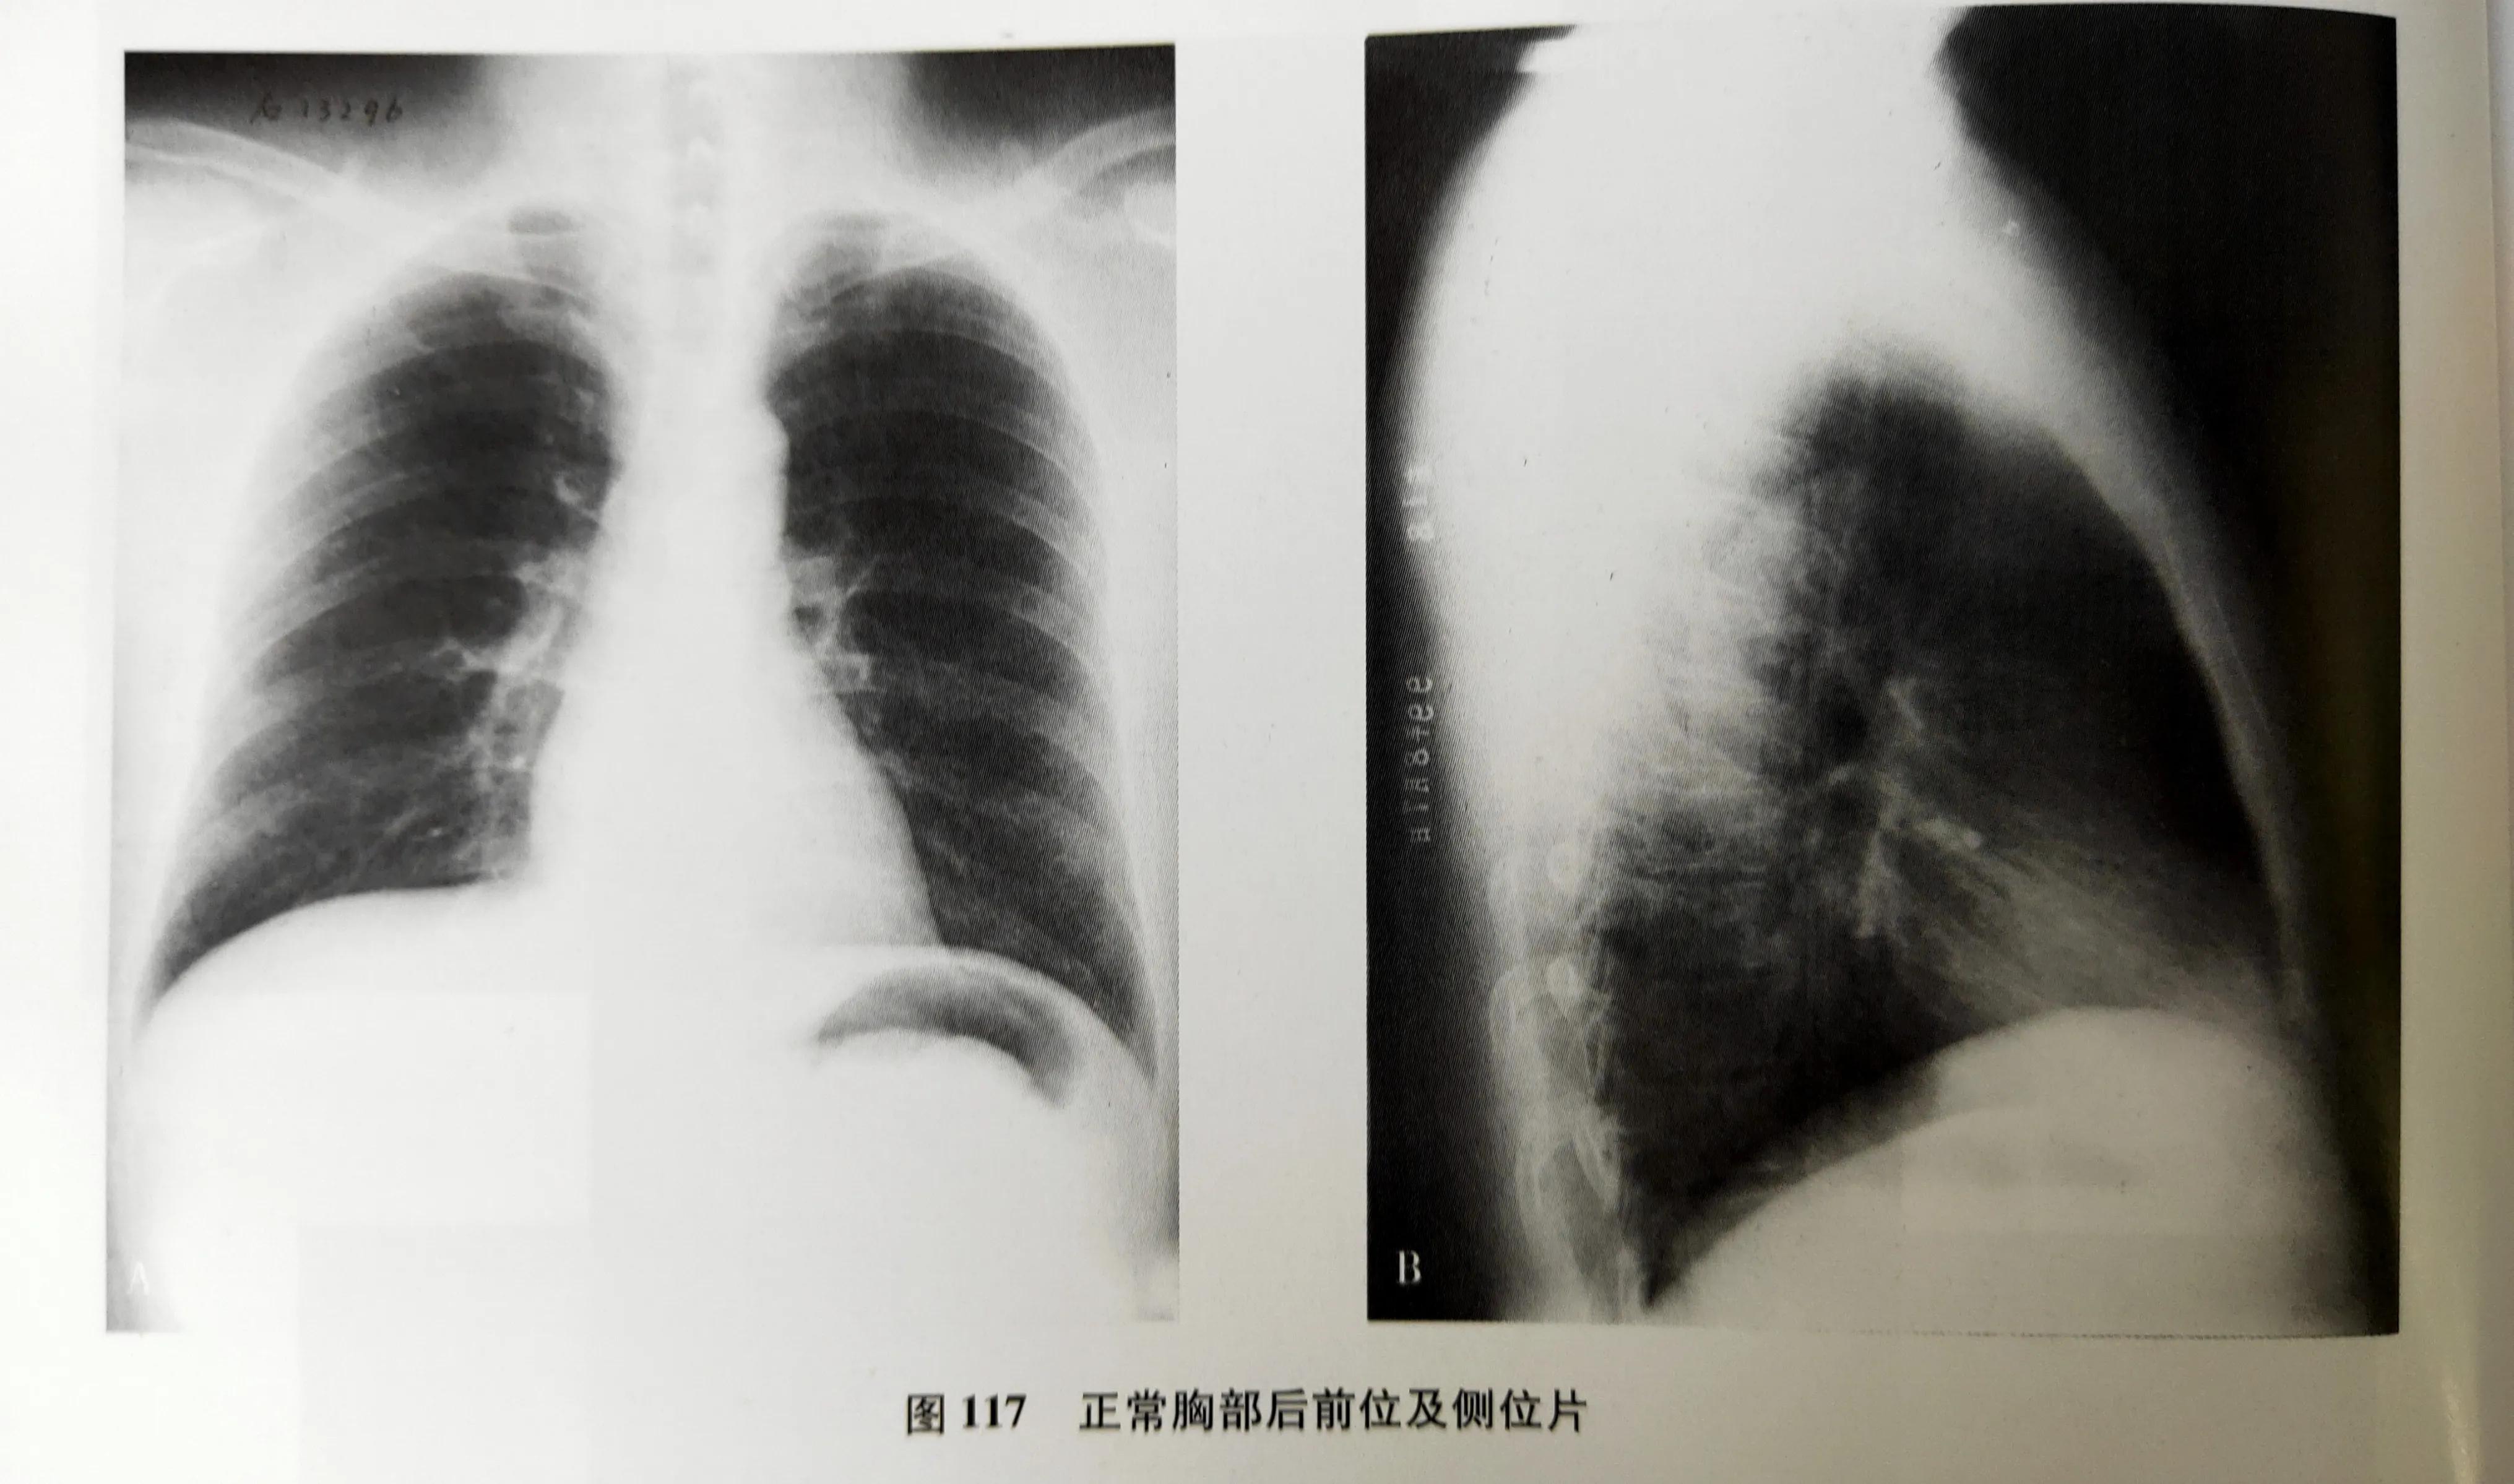

基于以上这些特性,人体组织和器官形态不同,厚度和密度各不相同,因此在X线片上就显示出黑白或明暗差别来。

在X线片上呈现的黑白灰等差别,可做四种密度:我们在片子上看到的白色的,是高密度,就是我们的骨头或钙化灶,如股骨、颅骨。我们看到的灰白色的,是中等密度,是我们的软骨、肌肉、神经、实质器官、结缔组织及体液。我们在片子上还能看到灰黑色的,这个是较低密度,是我们的脂肪组织。最后X线片上看到的黑色,是低密度,是气体,比如拍的胸片,如果是一大片黑,那很有可能是气胸了。

但是也有例外,因为成像的基本条件与物体的密度、厚度有关,如肋骨的密度高,但是它薄;而心脏大血管虽说是软组织,是属于中等密度,但是它厚啊,因此在X线片上显示的结果就是心脏大血管要比肋骨的白。